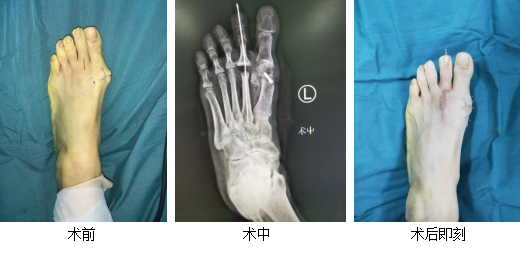

李大婶向邻居们打听哪家医院可以治疗拇外翻,得知betway在线登陆足踝外科特色微创治疗拇外翻,而且5月份为sararz“足踝关怀月”,手术有优惠。于是,李大婶来我院就诊,恰逢副院长、主任医师石荣剑坐门诊,石院长为其进行了详细检查。门诊摄片示:患者左足拇外翻角增大,约30度,第2跖趾关节间隙变窄,第1、2跖趾趾关节面硬化。初步诊断:左足后天性拇外翻畸形、左足第2跖趾关节炎。

石荣剑副院长亲自主刀,带领足踝医生团队为李大婶进行了“左足拇外翻畸截骨矫形内固定、第2跖趾关节成形术”。术中见第1跖骨头端胫侧部分骨质增生,局部关节面破坏,跖趾关节退变,切除增生的拇囊,第1跖骨远端做Chevron截骨,第1跖骨头颈部作侧方“V”形外移截骨,远端向外侧推移,纠正IMA及DMAA角,行内固定;切开暴露第2跖趾关节,见关节骨质增生、关节面破坏,松解关节囊,行内固定。手术顺利,仅用时1小时。